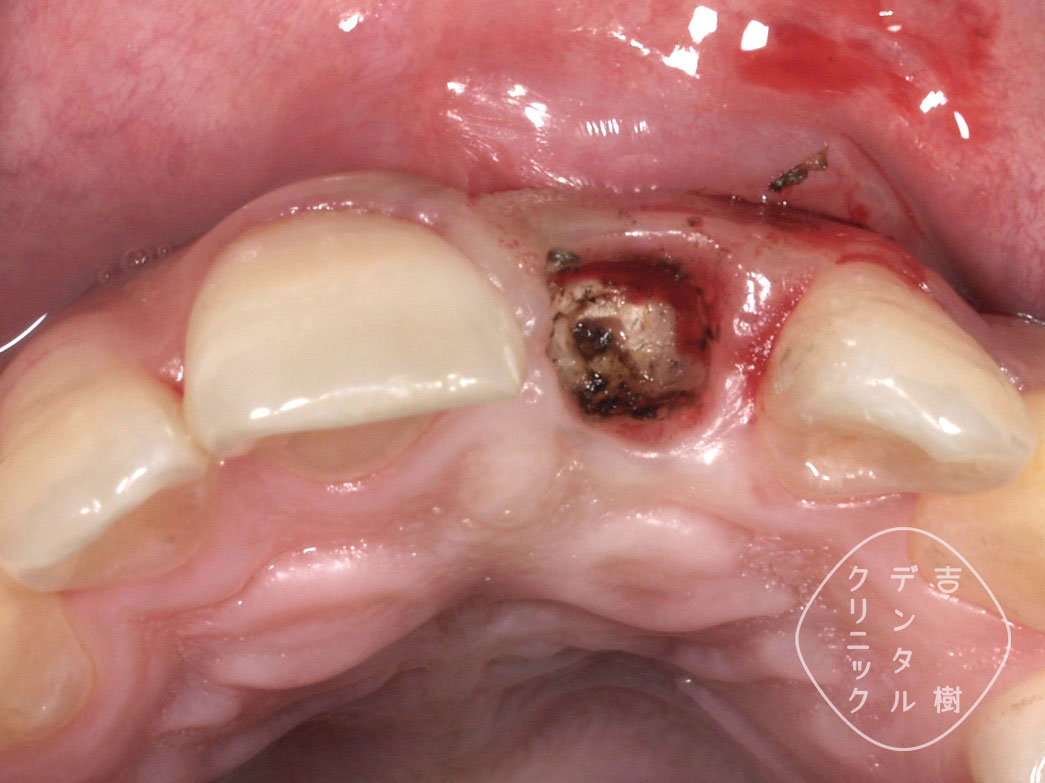

②歯茎の中に、歯の根が残っているのが目視できる

③エクストルージョンができるだけの歯根が確認できた